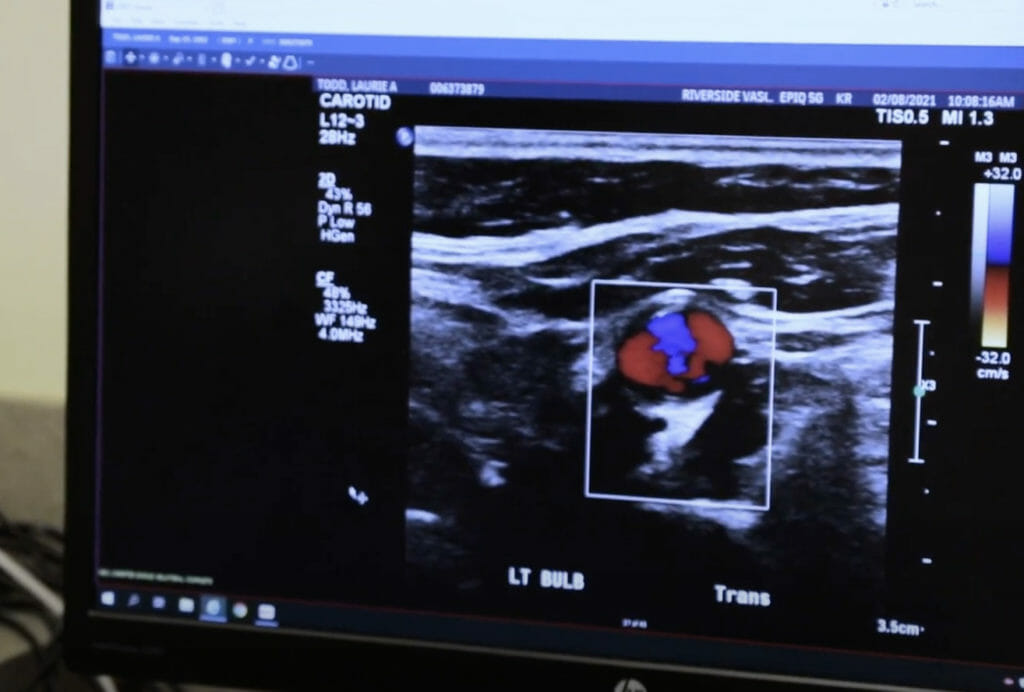

The heart and vascular services group at Riverside is a well grounded system that offers the latest in techniques in aiding with cardio-vascular disease.

Whether the blood vessels are narrowed or there is an aneurysm, they can help blood flow better.